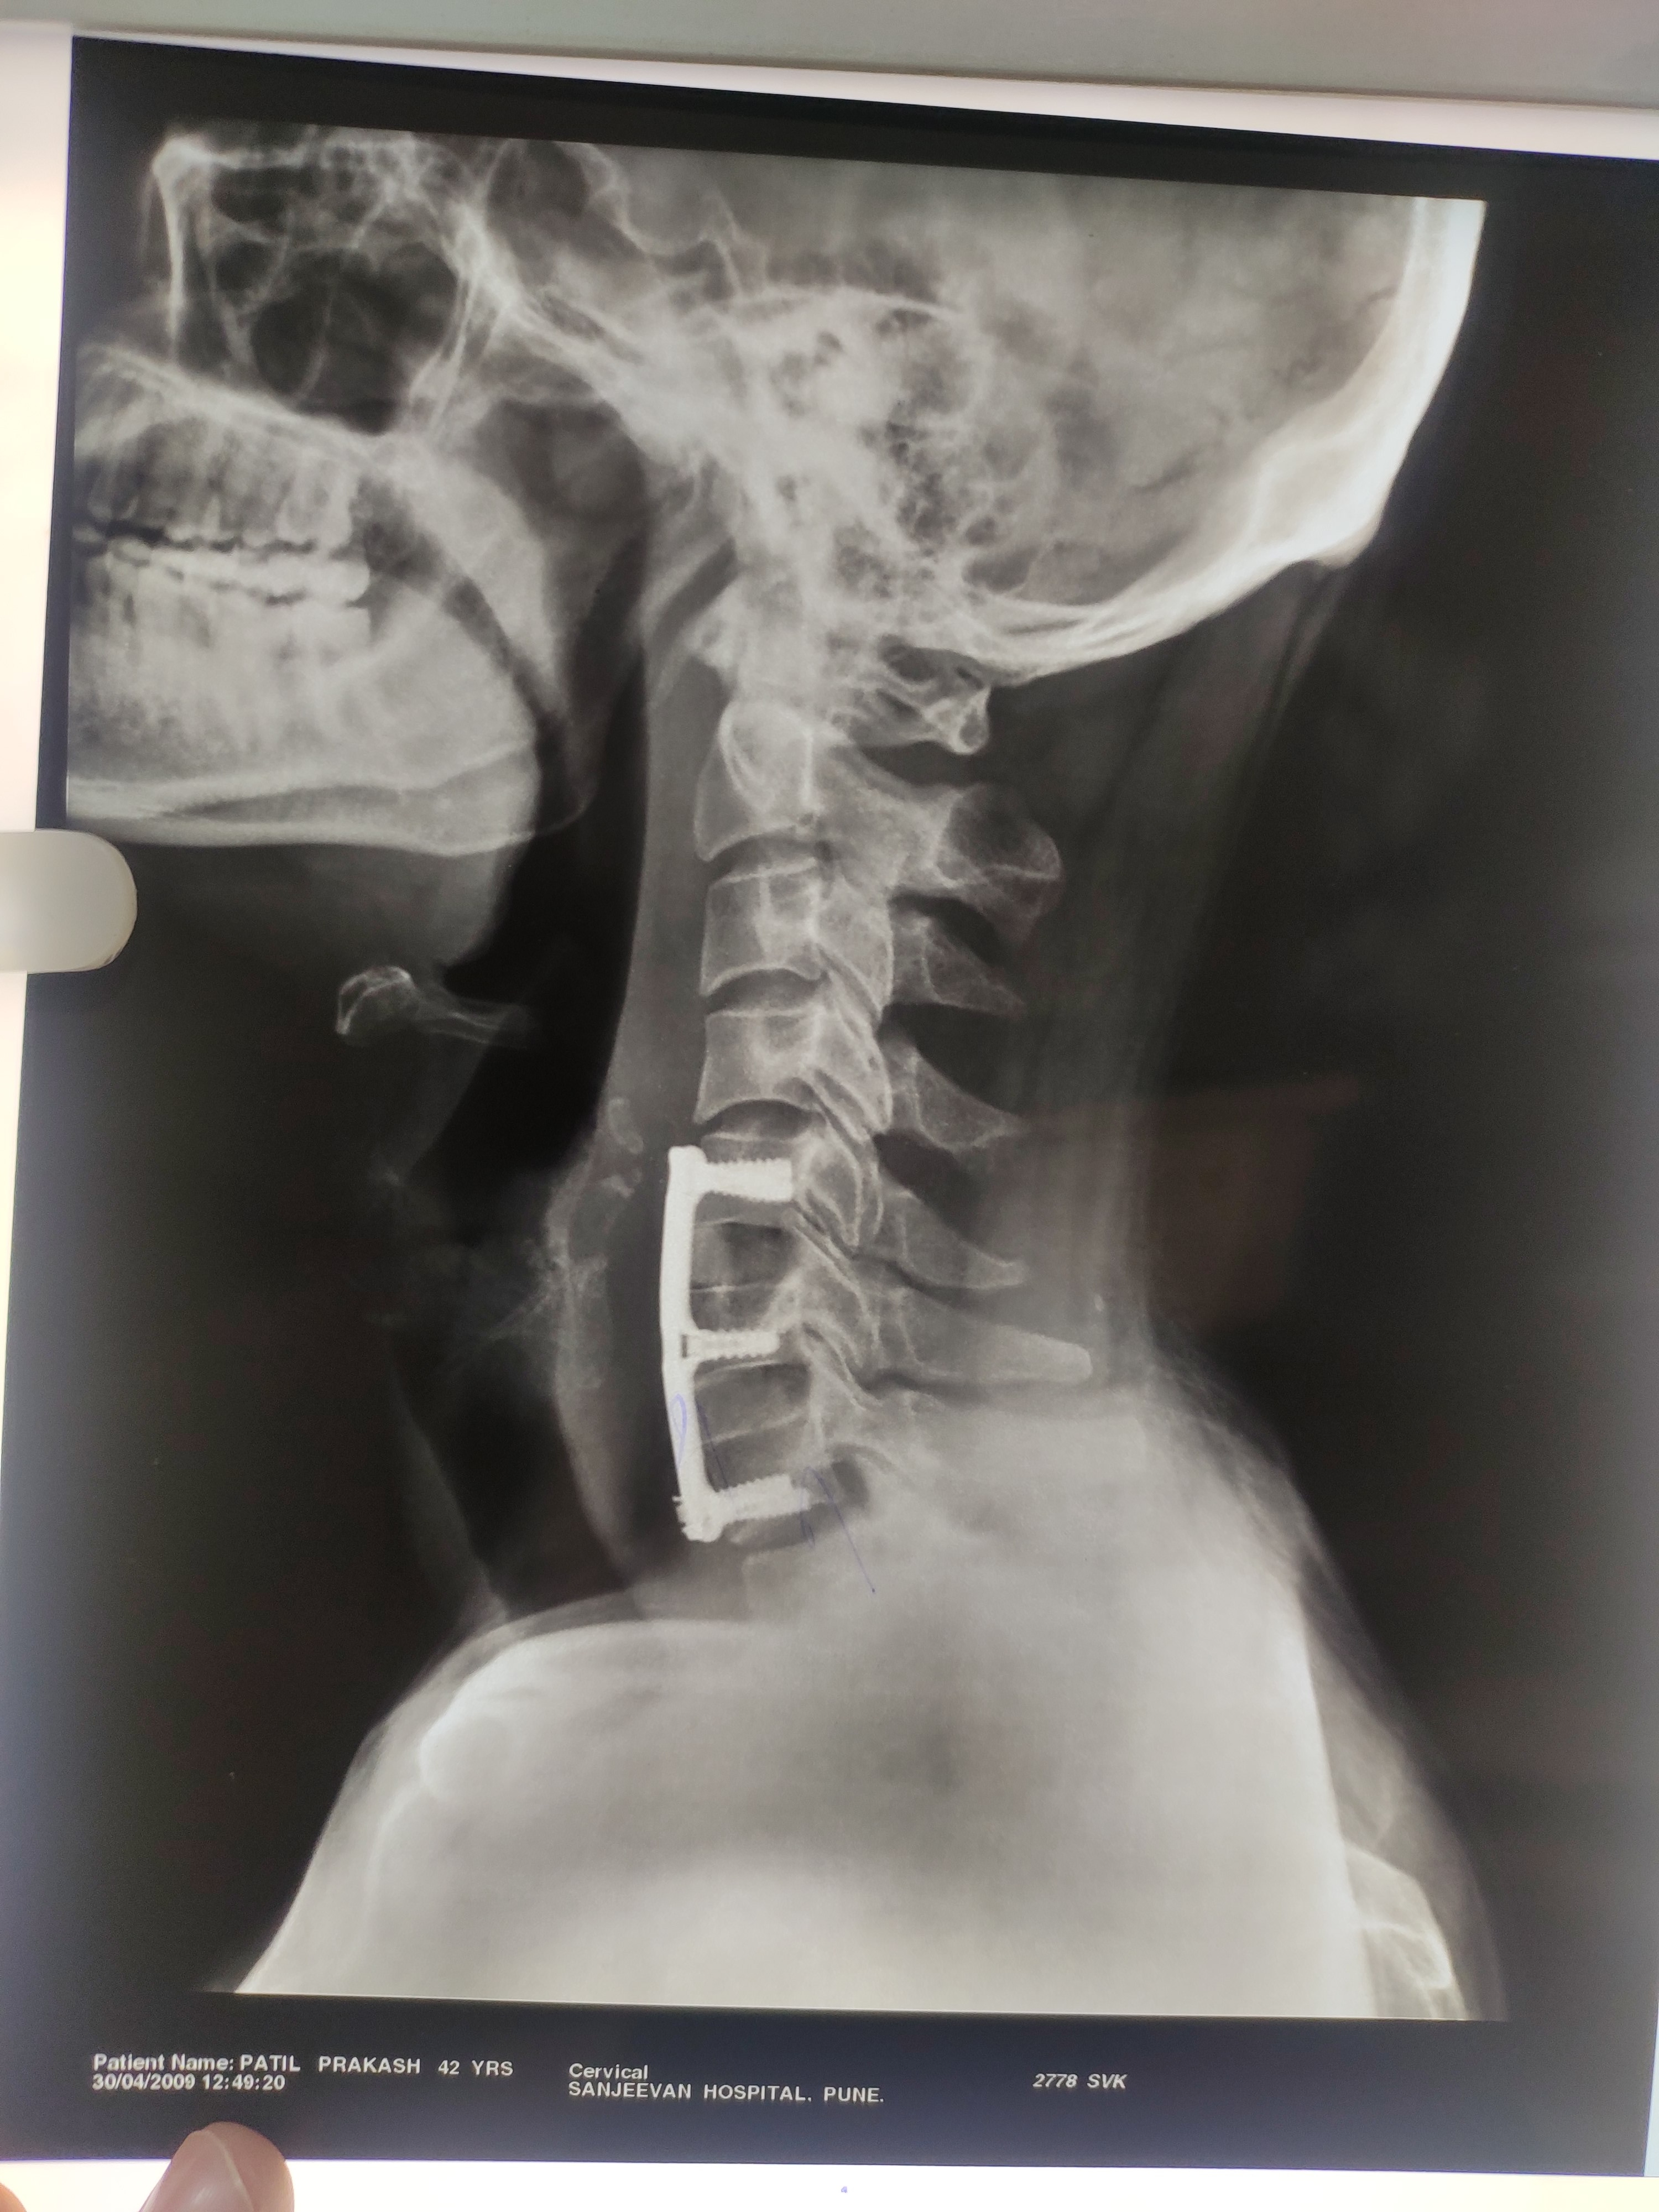

Dr. Sonawane Orthocare clinic is a centrally located Orthopedic Clinic In Pune city near Swargate at Hirabaug Business Centre, Hirabaug chowk, Tilak Road, Shukrawar peth and has easy accessibility from all parts of the city with multiple modes of travelling and enough parking spaces for patients’ own vehicles. Clinic is very modern and stylish and has air conditioned waiting area with comfortable sitting arrangement along with other amenities like TV, Wi-Fi, newspapers. There is hassle-free appointment and consultation system which is totally computerized. Patients get system generated appointment messages, reminders for follow-up dates and prescriptions through messages and emails. So its easy to keep track, keep and carry records and access it anywhere in the world. Clinic offers in-house digital X-ray, pathology tests and physiotherapy facilities at very reasonable rates. This makes the clinic a one stop destination for the patients they don’t need to go anywhere else for these facilities, saving lots of time and effort to get the treatment. We at Dr. Sonawane Orthocare clinic are committed for the best orthopedics care and proud to be one of the best orthopedics clinics in Pune.